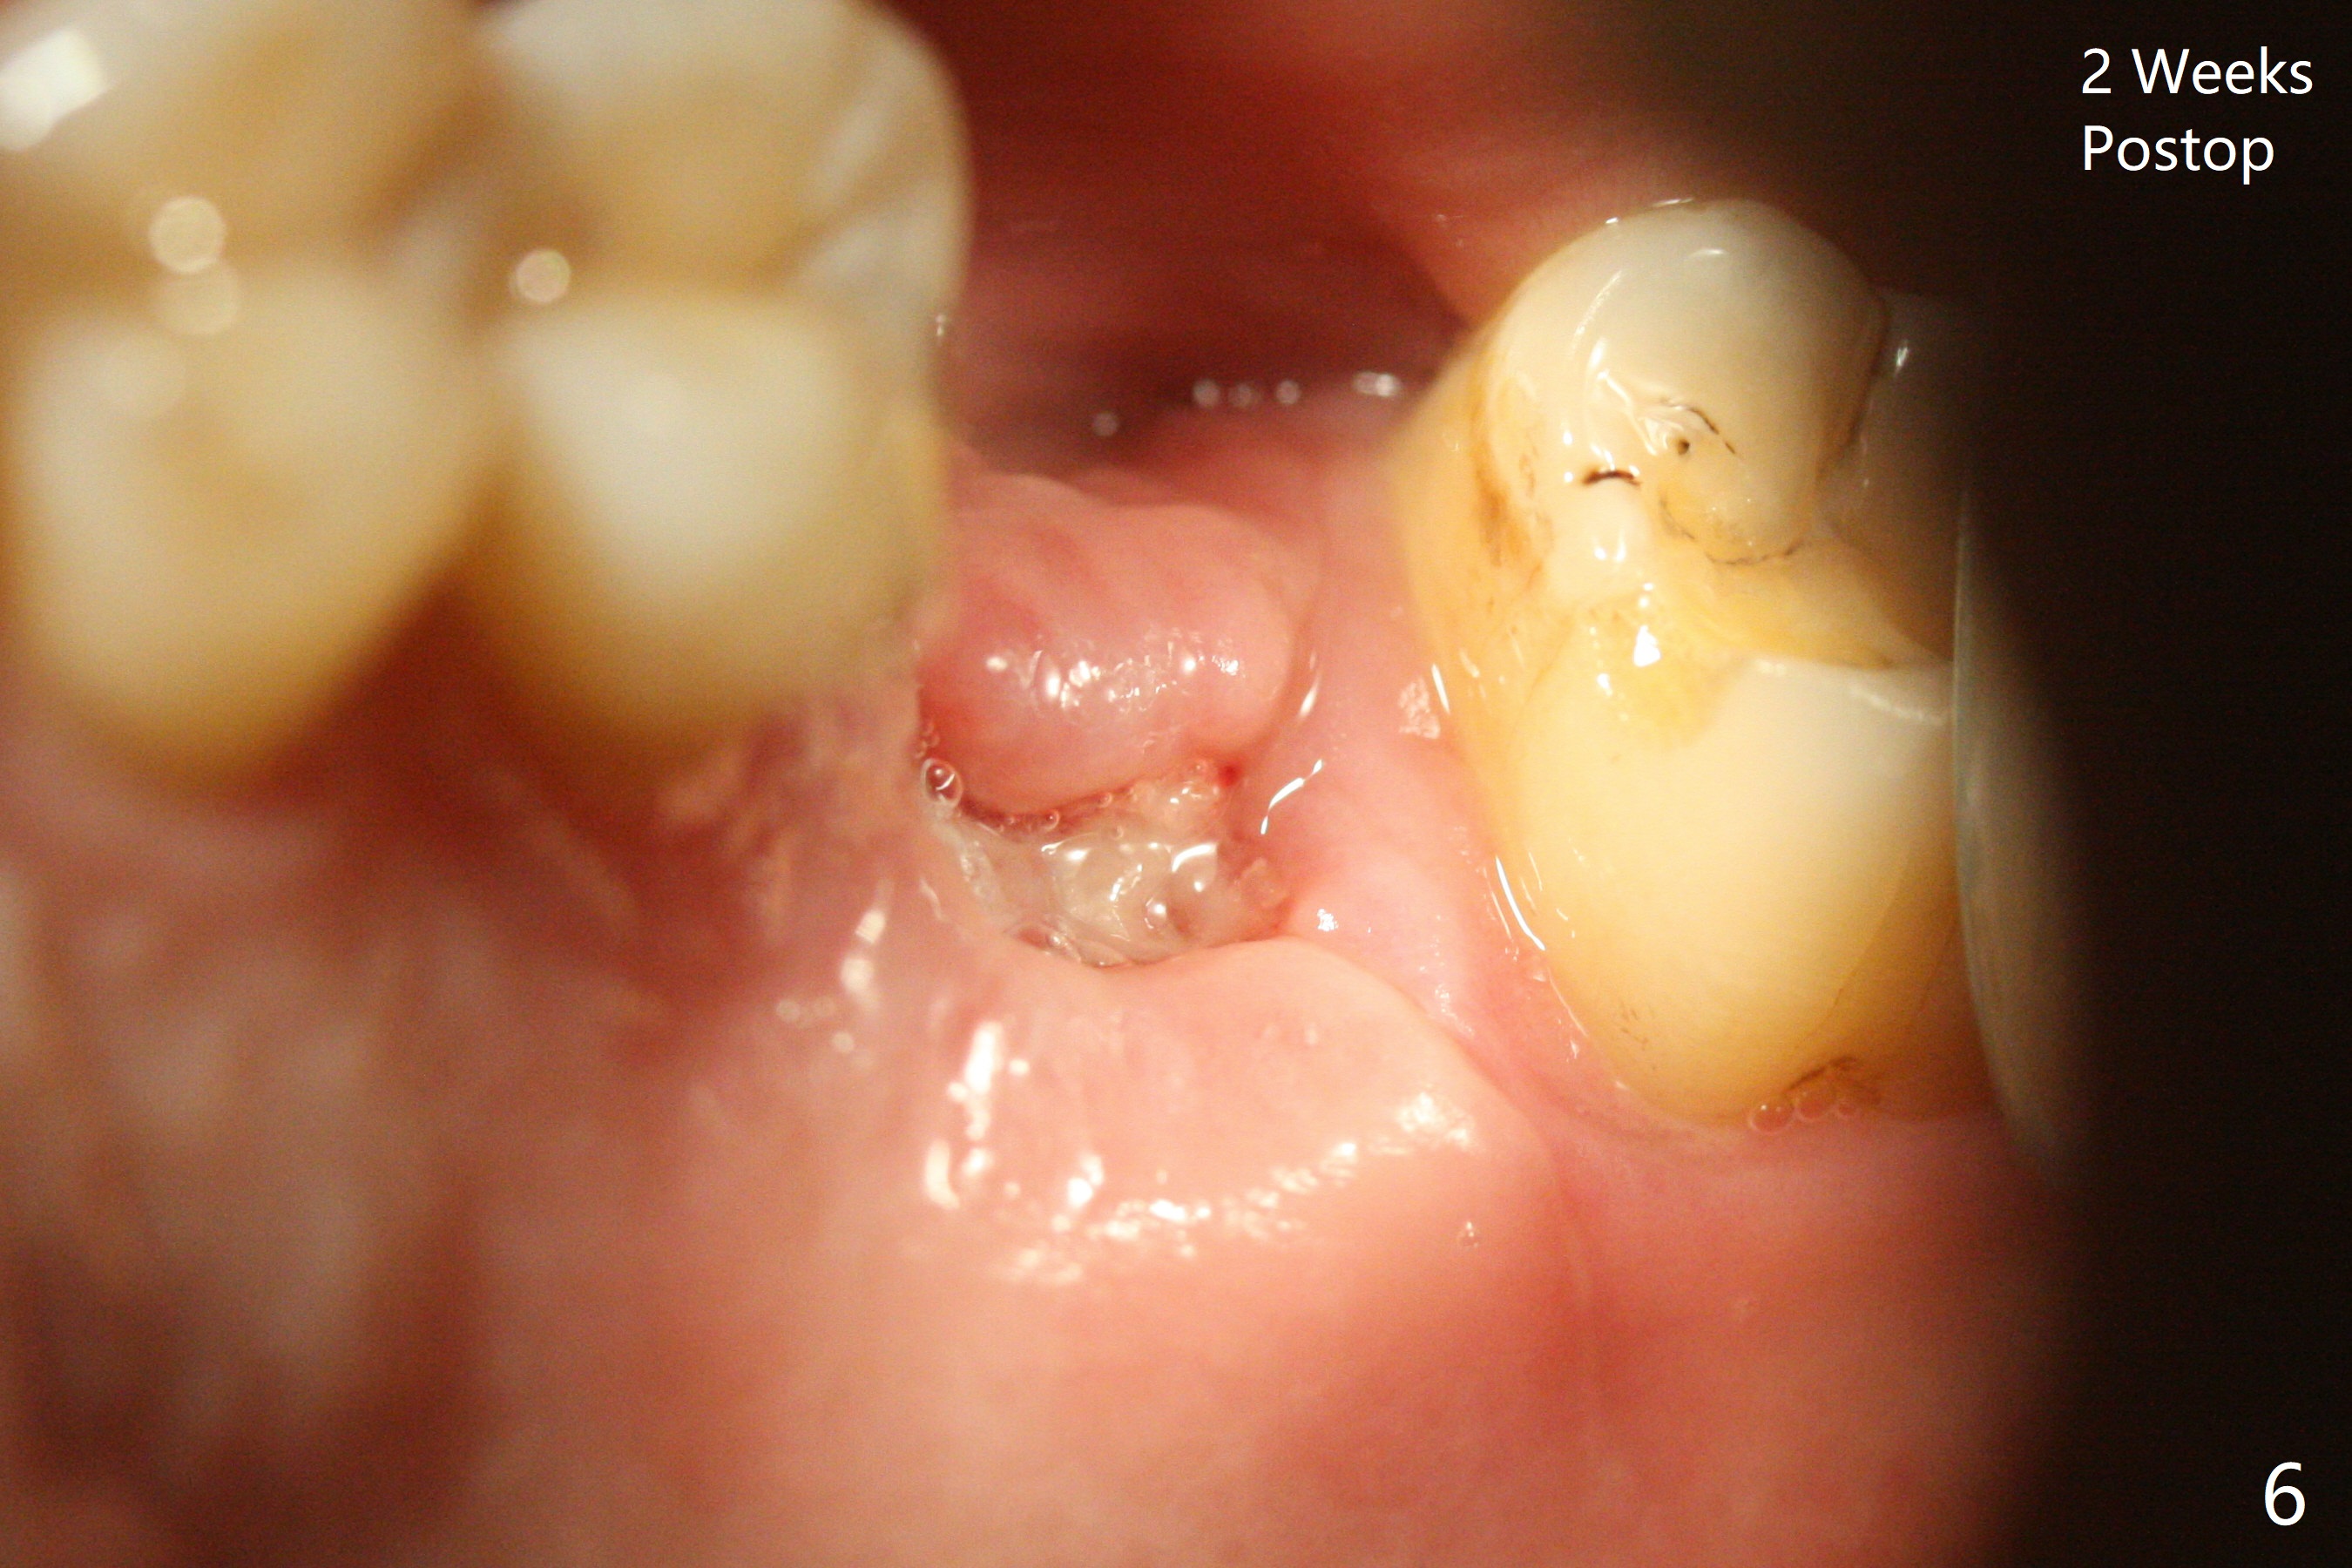

After using 4.5x5.3 mm and 3.5x7.3 mm drill at #14 with guide, the sinus floor is not perforated. When a 4.5x11 mm dummy implant is placed to the 2nd line (12 mm offset), the sinus membrane is perforated (Fig.1). A piece of PRF membrane and sticky bone are pushed into the sinus in an attempt for repair. A shorter implant is placed (5x7.3 (instead of 8.5) mm, Fig.2,3,5, as compared to Fig.3) to reduce postop sinus infection. In fact incision reveals palatal bony concavity. When the implant is placed, there is mild palatal thread exposure. With incision instead of tissue punch, it is easy to place bone graft over the small defect (Fig.3 *). The wound dehisces and heals 2 weeks postop (Fig.6). There is bone loss 6.5 months postop (Fig.7 *), corresponding to palatal thread exposure. After decortication and periosteal underscoring, cortical allograft mixed with ~.25 cc GEM21S is placed (Fig.8 *).